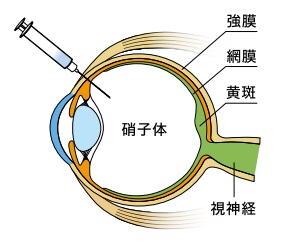

眼の構造と働きについて

私たちが物を見る、つまり外から眼に光が入ったとき、その情報は角膜→瞳孔→水晶体→硝子体と通過していき、最後に網膜に像が結ばれます。そこから視神経を介して情報が脳に伝わり、私たちは「見た」と感じます。 眼は、よくフィルムカメラに例えられます。水晶体がレンズにあたり、網膜はフィルムにあたるという関係ですね。

私たちが物を見る、つまり外から眼に光が入ったとき、その情報は角膜→瞳孔→水晶体→硝子体と通過していき、最後に網膜に像が結ばれます。そこから視神経を介して情報が脳に伝わり、私たちは「見た」と感じます。 眼は、よくフィルムカメラに例えられます。水晶体がレンズにあたり、網膜はフィルムにあたるという関係ですね。

黄斑・中心窩について

黄斑とは、網膜の中心部にあり、視力ともっとも深いかかわりを持っています。物を見たときのその物の大きさや形、奥行きなど、視覚情報の大半が、黄斑で認識されています。ここで障害が起こると、当然ながら視力の低下が引き起こされます。 黄斑のさらに中心には、「中心窩」があります。こちらはさらに重要な部分であり、障害されたときにはより大幅な視力低下を招きます。

黄斑とは、網膜の中心部にあり、視力ともっとも深いかかわりを持っています。物を見たときのその物の大きさや形、奥行きなど、視覚情報の大半が、黄斑で認識されています。ここで障害が起こると、当然ながら視力の低下が引き起こされます。 黄斑のさらに中心には、「中心窩」があります。こちらはさらに重要な部分であり、障害されたときにはより大幅な視力低下を招きます。

抗VEGF薬治療(硝子体内注射)とはどのような治療?

導入期

まず月に1回、抗VEGF治療薬を白目部分から硝子体へと注射します。これを3回、3ヵ月にわたって継続します。

維持期

1ヵ月に1回、眼の状態を観察・検査しながら、必要に応じて抗VEGF治療薬を同様に注射します。